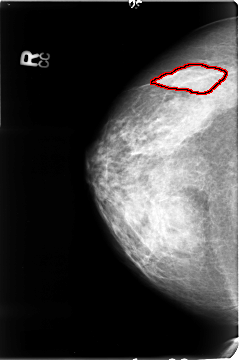

B_3048_1.LEFT_CC

FILE: B_3048_1.LEFT_CC.OVERLAY

TOTAL_ABNORMALITIES 1

ABNORMALITY 1

LESION_TYPE MASS SHAPE IRREGULAR-ARCHITECTURAL_DISTORTION MARGINS ILL_DEFINED-SPICULATED

ASSESSMENT 4

SUBTLETY 4

PATHOLOGY MALIGNANT

TOTAL_OUTLINES 1

BOUNDARY